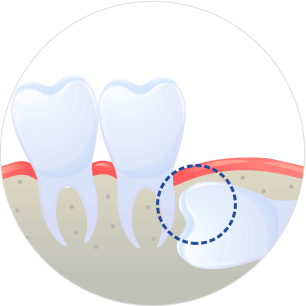

사랑니가 겉으로 보이지 않는 경우

이를 매복이라 부르는데, 치아주머니에 물이 차서 물혹이 되거나 세포가 변형될 수 있기 때문에 빠른 시일 내에 발치하는 것을 권장합니다.